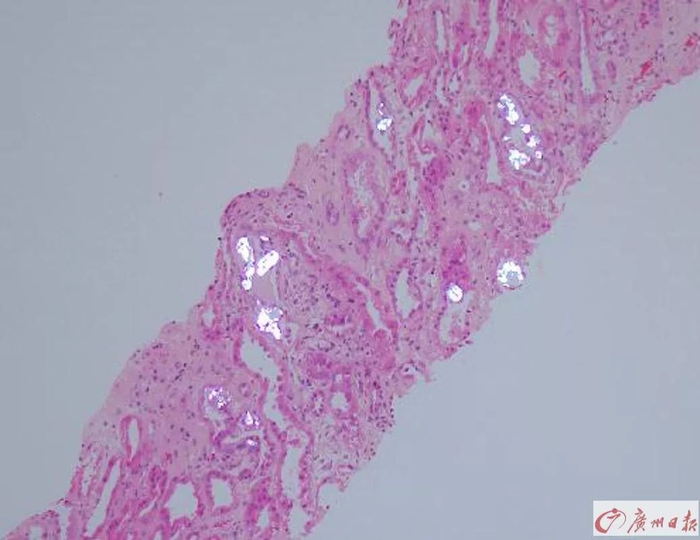

两位患者的肾穿刺病理活检结果都提示——符合急性肾小管损伤。在住院将近半个月后,两人才陆续出院。“没想到喝了这个杨桃酒后果这么严重,以前都不知道杨桃有肾毒性啊。以后再也不敢喝了。”出院前张先生说。

肾小管造影显示存在大量结晶沉淀物。(银白色部分)